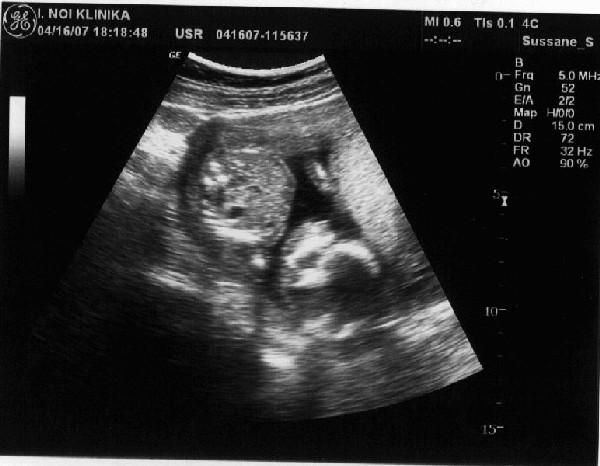

És az UH kép. Fejjel lefelé van. Ha jobban megnézegetitek az első képet látszik hogy az egyik keze az arca előtt van, ökölbe, tehát szerintem cumkizik :).

Kép

A másodikon a kis pisze orra a lényeg.